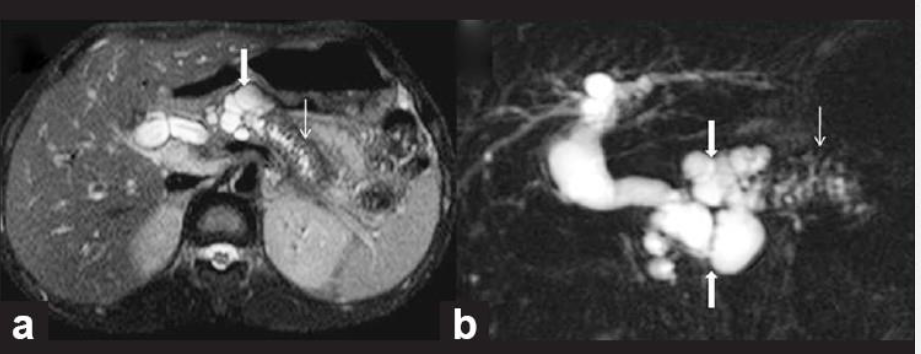

מהו הממצא

A

פסואודוציסטה בלבלב- דם,אפיתל ושאריות של חלבון שהצטבר

How well did you know this?